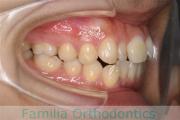

でこぼこと口元が出ている横顔が気になるとのことで来院されました。重度の叢生(ガタガタ)と側方へのズレがあるため、アンカースクリューを併用したマルチブラケット法にて治療を行いました。3年弱、35回程度の通院をしていただきました。叢生が強いため、部分的にガタガタが再発・後戻りするリスクが高いケースでした。

- ≫治療前

上顎

下顎

前歯の関係など

右側

正面

左側